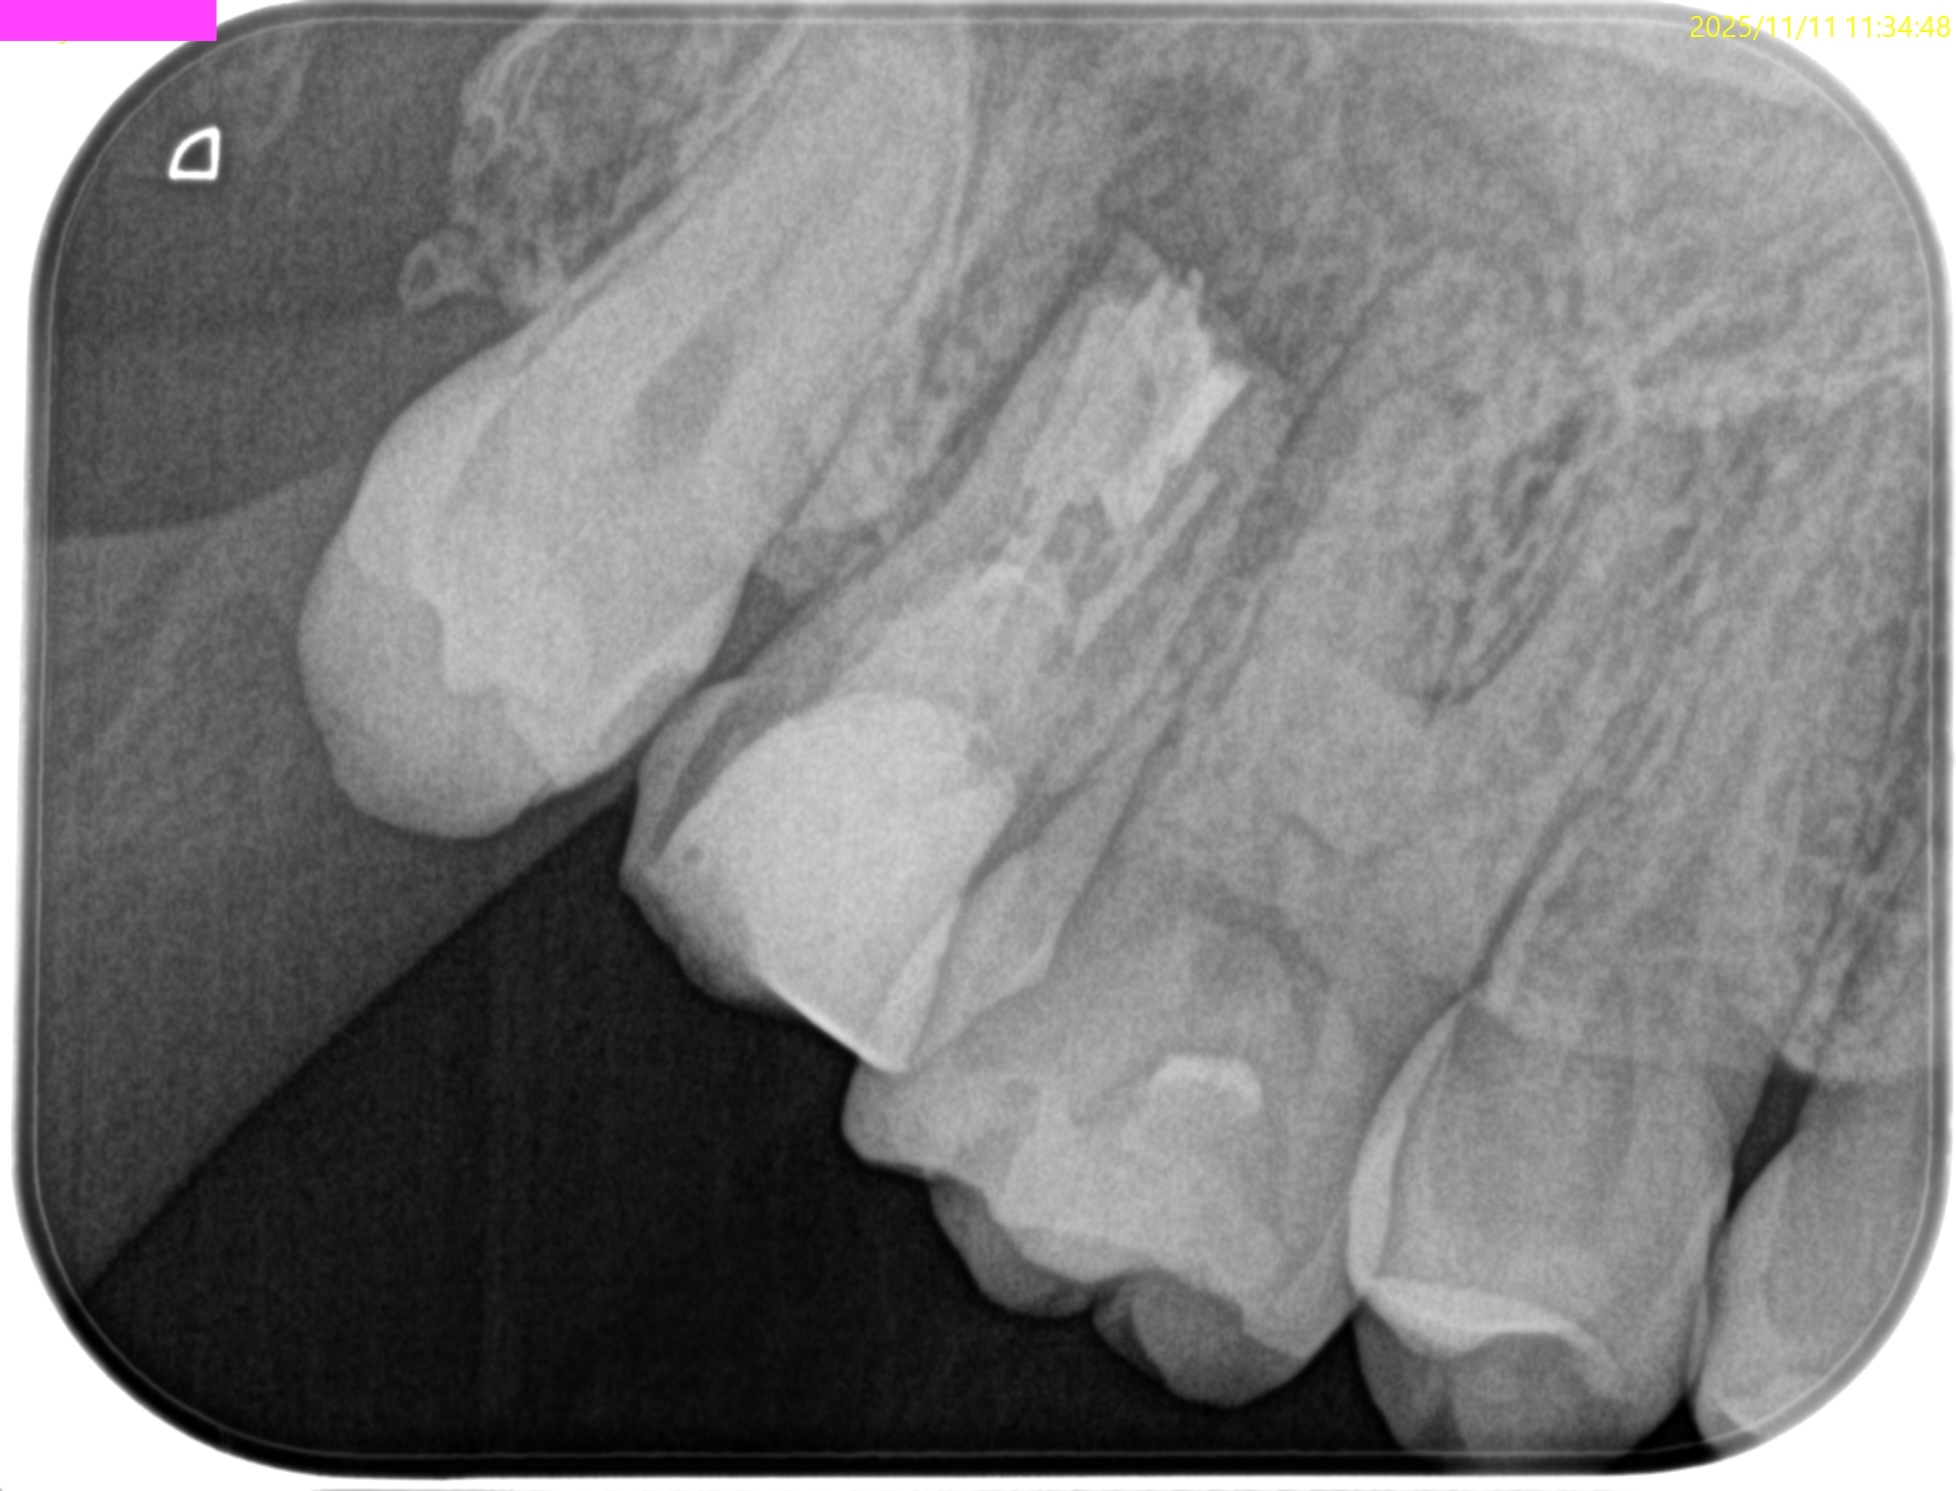

Pre-op Endo test(2025.11.11)

PA(2025.11.11)

Pre-op Endo Diagnosis(2025.11.11)

Pulp Dx: Previously treated

Periodical Dx: Symptomatic apical periodontitis

Recommended Tx: Intentional Replantation